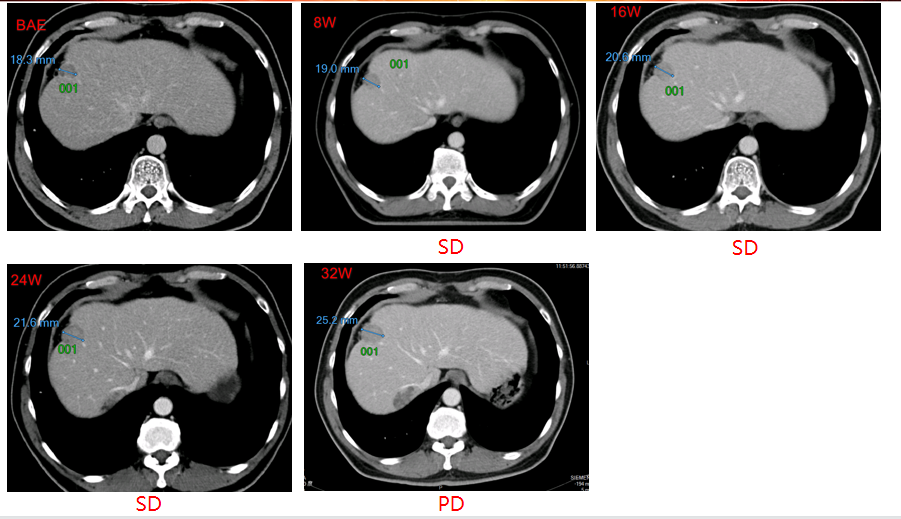

非靶病灶影像学改变:

2016-11-15,首次口服多纳非尼治疗(0.2g,每日两次口服),肿瘤些许增大,疗效评估为疾病稳定(SD),继续接受多纳非尼治疗,肿瘤持续稳定。经独立审查委员会(IRC)评估的无进展生存期(PFS)为7.5个月,经研究者评估的PFS为9.3个月。